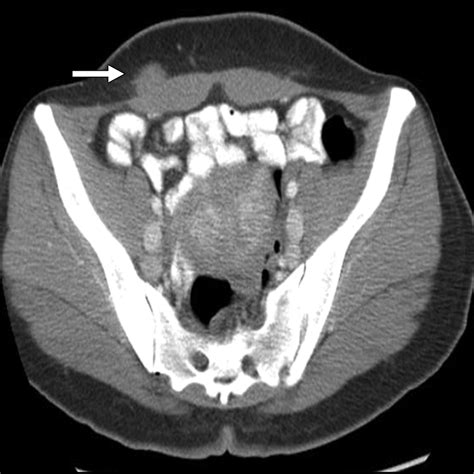

CT Scan High-resolution cross-sectional images to pinpoint the exact location and nature of the mass.

Because the abdomen contains a dense arrangement of structures, relying on a physical "self-exam" is rarely sufficient. A doctor will typically correlate physical findings with diagnostic imaging. For instance, an ultrasound might distinguish between a solid tumor and a fluid-filled cyst, while a CT scan provides the necessary detail to assess whether the mass in stomach involves surrounding blood vessels or lymph nodes. In some cases, a biopsy—the removal of a small tissue sample—is the only definitive way to characterize the cellular nature of the mass.